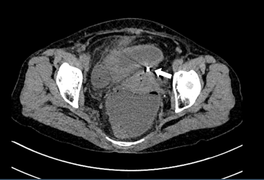

Bác sĩ Lê Thị Anh Đào, Trưởng khoa Phụ ngoại A5, Bệnh viện Phụ sản Hà Nội cho biết, kết quả chụp MRI phát hiện bé có hai buồng tử cung, hai cổ tử cung, ứ dịch trong lòng âm đạo bên trái.

Theo bác sĩ Lê Thị Anh Đào, tử cung đôi có 2 cổ TC một cổ TC thông vào âm đạo bình thường, một cổ TC thông vào âm đạo dị dạng bị bịt kín còn được gọi là âm đạo chột là dị tật đường sinh dục khá nghiêm trọng. Tình trạng này có thể dẫn tới ứ máu kinh và lâu ngày gây viêm nhiễm và vô sinh, hưởng tới cuộc sống sinh hoạt vợ ngoài ra cũng ảnh hưởng tới đời sống vợ chồng.